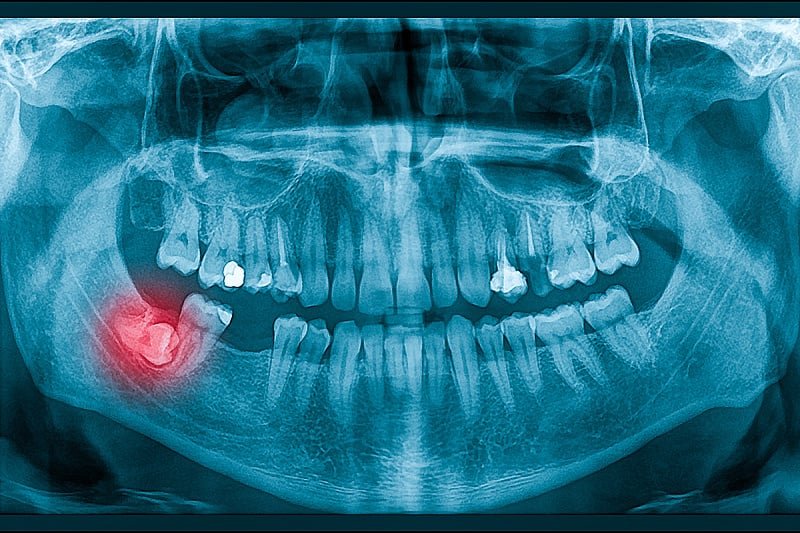

Истражувањето се фокусира на ген-1, поврзан со хиперсензитивност на матката (USAG-1), антитело познато дека го инхибира развојот на забите кај цицачите. Во 2021 година научниците од Универзитетот во Кјото, кои исто така се вклучени во тековните испитувања, идентификуваа моноклонално антитело, способно да ја наруши интеракцијата на USAG-1 со коскените морфогенетски протеини (BMPs), кои играат клучна улога во формирањето на забите.

Сега научниците го тестираат лекот во 11-месечна студија, во која учествуваа 30 машки учесници на возраст од 30 до 64 години на кои им недостасува барем еден заб. Лекот се администрира интравенски за да се процени неговата безбедност и ефикасност. Не се забележани негативни ефекти во претходните студии на животни.